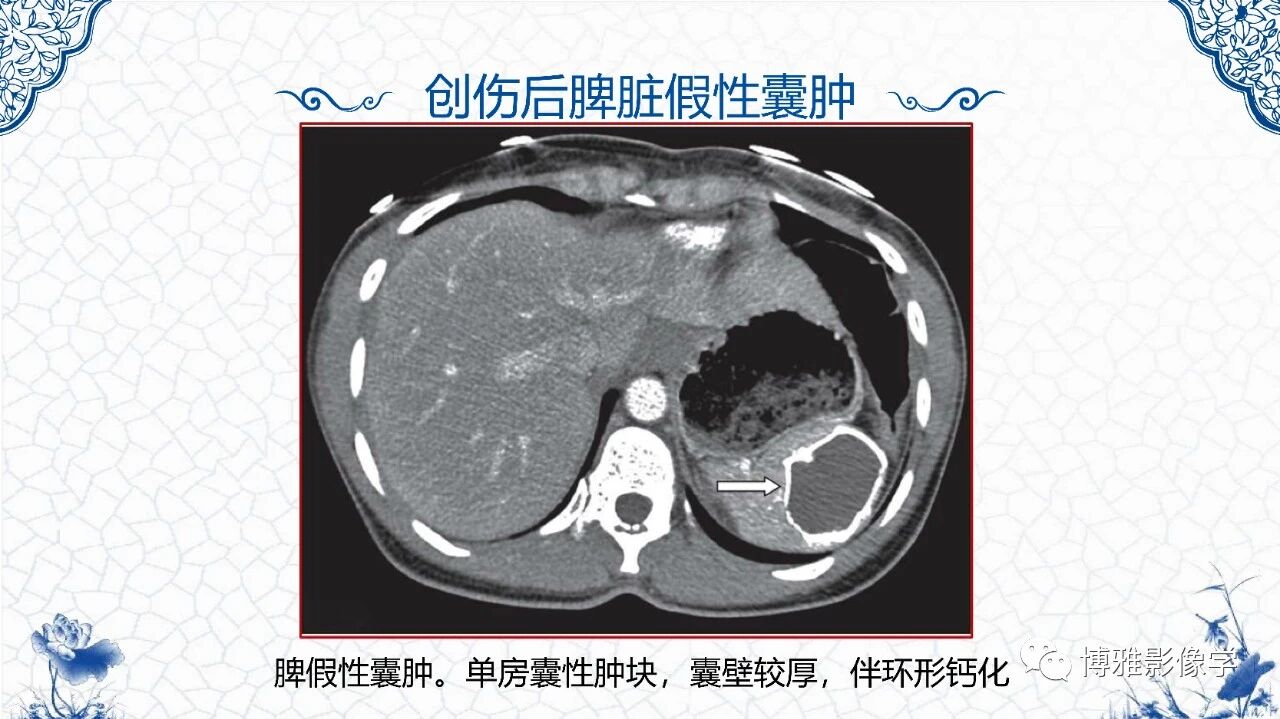

[腹盆] 脾脏非肿瘤影像诊断

脾脏非肿瘤影像诊断